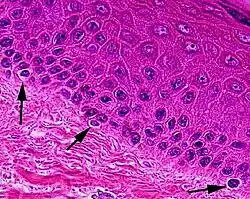

Melanocytes are melanin-producing neural crest-derived[3] cells located in the bottom layer (the stratum basale) of the skin's epidermis, the middle layer of the eye (the uvea),[4] the inner ear,[5] vaginal epithelium,[6] meninges,[7] bones,[8] and heart found in many mammals and birds.[9] Melanin is a dark pigment primarily responsible for skin color. Once synthesized, melanin is contained in special organelles called melanosomes which can be transported to nearby keratinocytes to induce pigmentation. Thus darker skin tones have more melanosomes present than lighter skin tones. Functionally, melanin serves as protection against UV radiation. Melanocytes also have a role in the immune system.

Typically, between 1000 and 2000 melanocytes are found per square millimeter of skin or approximately 5% to 10% of the cells in the basal layer of epidermis. Although their size can vary, melanocytes are typically 7 μm in length.

Both lightly and darkly pigmented skin contain similar numbers of melanocytes,[12] with difference in skin color due to differences the packing of eumelanin into the melanosomes of keratinocytes: those in dark-toned skin are "packaged into peri-nuclear distributed, ellipsoid" melanosomes while those light-tone skin are "assembled into clustered small, circular melanosomes".[13] There are also differences in the quantity and relative amounts of eumelanin and pheomelanin.[13] Pigmentation including tanning is under hormonal control, including the MSH and ACTH peptides that are produced from the precursor proopiomelanocortin.